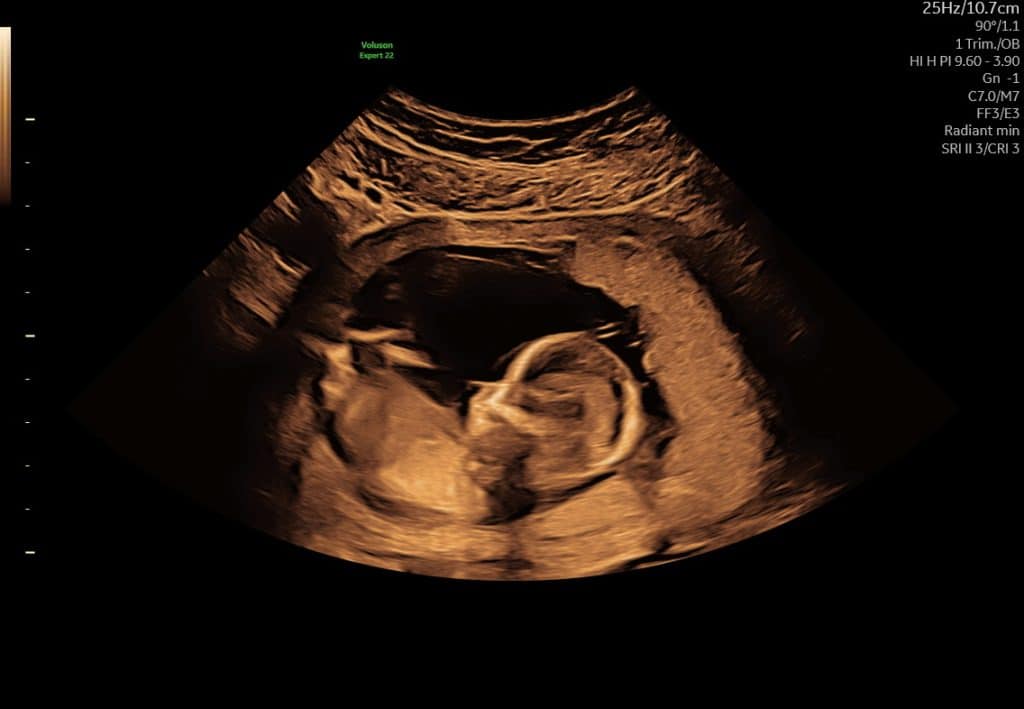

Ultralyd uge 12 – mere detaljeret anatomi

Omkring uge 12 er fosteret tydeligt udviklet. Man kan se:

Nakkefold (ved relevant scanning)ode, at mange vælger scanning i forbindelse med risikovurdering, fx nakkefoldsscanning, hvis man ønsker det. Billedkvaliteten er ofte god, men fosteret er stadig relativt lille.

Arme og ben

Bevægelser

Ultralydsscanning uge 11

Ultralydsscanning uge 10

Eksempel på ultralyd i uge 11–13. Fosterets bevægelser kan ofte ses tydeligt.